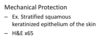

Neutrophil Migration:

a. white blood cells in blood vessel

b. after diapedesis

c. after chemotaxis